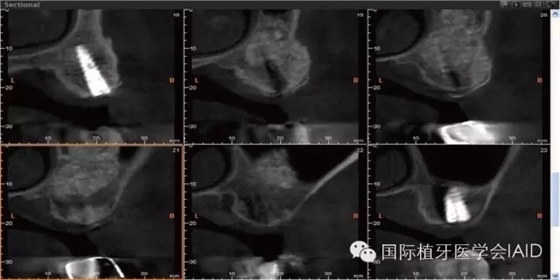

在植牙手術(shù)執(zhí)行之前,需要進(jìn)行全口檢查與軟硬組織的評(píng)估。口外石膏模型與cone beam CT資料搜集有助于治療計(jì)劃的擬定。在石膏模型上進(jìn)行diagnostic wax up有助于決定植體上假牙前后關(guān)系、頰舌側(cè)位置、咬合高度、及植體與植體上假牙的高度比例。使用Cone beam CT(CBCT)可以容易了解手術(shù)區(qū)硬組織條件,如Septum、骨頭高度及寬度、骨頭密度、神經(jīng)血管位置等。分析以上數(shù)據(jù)后,較容易得到可預(yù)期性的結(jié)果。

初期穩(wěn)定度在第一及第二類型的案例(>9mm; 6mm-9mm) 可以較容易達(dá)到,故通常以crestal approach進(jìn)行手術(shù)。Lateral window術(shù)式在第三型(3mm-6mm)較被建議。 若是前三個(gè)類型的初期穩(wěn)定度達(dá)到35Mpa,可以考慮當(dāng)次放置植體。若骨頭條件屬于第四型(<3mm),Lateral approach 比較建議使用,而植體可考慮等到Grafted Bone較成熟時(shí)再置入。(Fig. 1 & 2)術(shù)式的選擇與骨頭高度有密切的關(guān)系,當(dāng)骨頭垂直高度小于3 mm(于兩顆植體中),植體應(yīng)考慮 Bone graft穩(wěn)定后再植入。

Lateral window的區(qū)域及范圍可借由CBCT和解剖構(gòu)造位置來(lái)決定。理想的window骨切線前緣及下緣位置應(yīng)離sinus底部(floor)其前緣(anterior wall)3-5 mm (Fig. 5 & 6)。